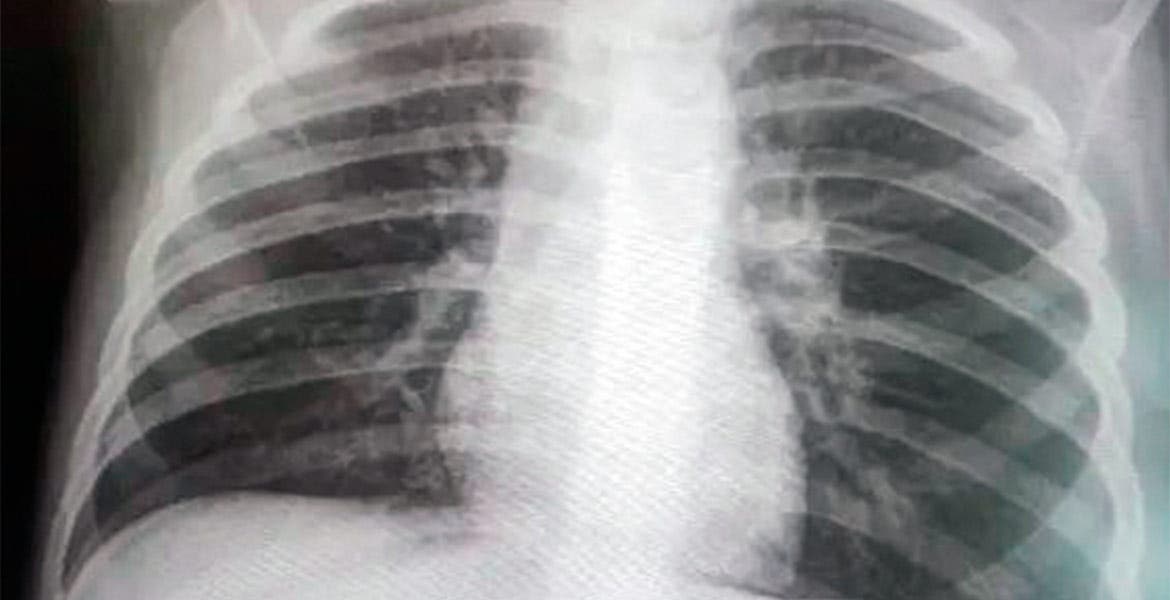

Cuernavaca, MORELOS.- Autoridades municipales indican que han aumentado los fallecimientos por “neumonías atípicas”, por lo que consideran que no coinciden las cifras de contagios por COVID-19 que informan autoridades de Salud estatal y federal.

Suben decesos por neumonías

“En el registro civil se han registrado muchas defunciones por neumonías atípicas o por cuestiones relacionadas; contabilizando sería la tercera causa de decesos que se registran actualmente”, declaró. iCumplen